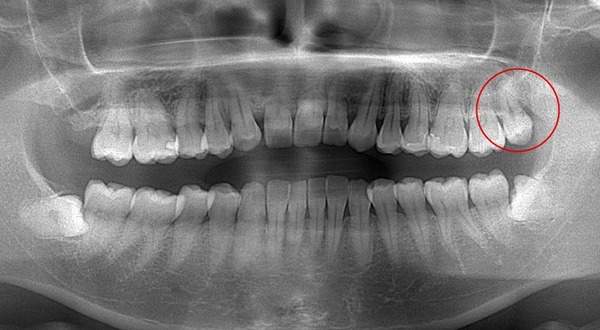

麻布十番歯科で親知らずが横向きに生えて歯ぐきが腫れている症例の口腔内写真のイメージ

親知らずを抜くのに痛みを伴いやすいものが写真とレントゲンにあるような真横にはえているもの、もしくは斜め下にはえている下顎の親知らずです。また、根が曲がっていたり、数が多いほど抜くのが難しい経口にあります。

この場合、歯ぐきを切ったり、歯を囲っている周りの骨を削って抜いていかなければなりません。

そのため、抜歯後は腫れや痛みが伴いやすくなります。 抜歯中は麻酔を行いますが、骨が硬い方は麻酔がなかなか効かないこともあります。そのため痛みを伴うことがあります。

また上顎でも根の数が多かったり曲がっていたり、または上顎洞といって、お鼻の横にある副鼻腔と交通しているような親知らずでは、痛みが伴うことがあります。